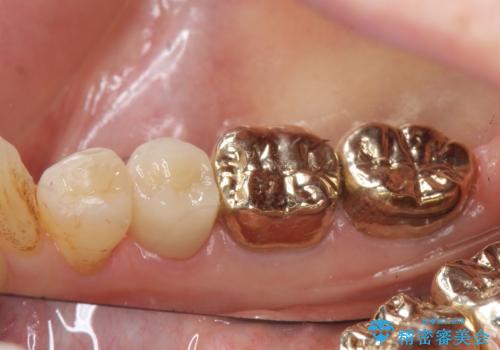

口腔外から見えやすい 4 番目、5 番目の歯はセラミックによる審美的な治療を行い、6 番目、 7 番目の奥歯 2 歯は適合性に優れたPGA(ゴールド)クラウンによる治療を行いました。

オールセラミッククラウンについて

今回用いたオールセラミッククラウンはジルコニアフレームという白い素材の上にセラミックを盛っているため、審美性が非常に高いのが特徴です。

また、ジルコニアは人工ダイヤモンドの材料にも使われているほど高い強度を持っており、そのためオールセラミッククラウンは審美性だけでなく、奥歯やブリッジの補綴も可能とするクラウンです。